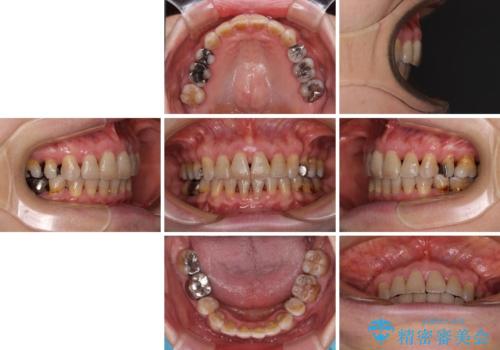

閉じにくい口元を改善したい ワイヤー装置での抜歯矯正

- 突出した口元を引っ込めることを希望して来院された患者様です。

上下左右第一小臼歯4本を抜歯して、口元を改善するワイヤー矯正を行うこととしました。